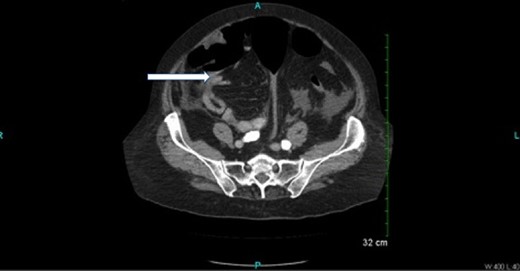

CT scan (Figs 2 and 3) revealed a large hematoma at the lateral margin of the spleen that displaced the spleen medially and compresses its lateral margin. A moderate amount of relatively low attenuation fluid also tracked into the right paracolic gutter and perihepatic space. There also appeared to be a 3.5 × 2.5 cm broad-based mass along the wall of the right colon. The CT scan of the chest also demonstrated a pulmonary embolus in a subsegmental artery of the right upper lobe. Given these findings, the patient was aggressively resuscitated with packed red blood cells and taken emergently to the operating theatre.

Oral and intravenous contrast enhanced CT of the abdomen demonstrating air within the colonic lumen and a 3.5 × 2.5 cm broad-based mass along the wall of the right colon (white arrow).

Oral and intravenous contrast-enhanced CT of the abdomen demonstrating air within the colonic lumen and a large haematoma at the lateral margin of the spleen that displaced the spleen medially, compressing its lateral margin. A moderate amount of relatively low attenuation fluid is also seen tracking into the right paracolic gutter and perihepatic space.